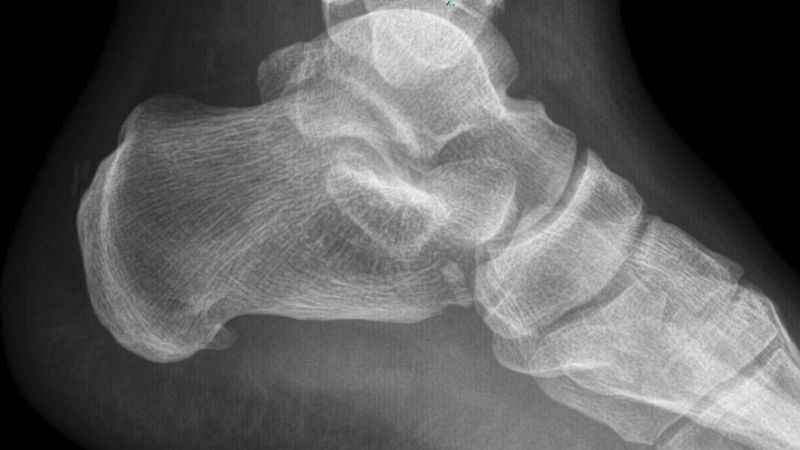

Tedavi yöntemleri hakkında da açıklamalarda bulunan Prof. Dr. Demiralp, “Ağrılı topuk sendromunun nedenlerine baktığımız zaman öncelikli olarak nedenini araştırmamız gerekir. Biz öncelikli olarak hastalarımızın şikayetlerini dinliyoruz. Ardından muayene yapıp gerekirse röntgen çekiyoruz. Burada en sık karşımıza çıkan plantar fascia dediğimiz ayakta gerginliktir. Ayakta yaşanan bu gerginliğin ardından uzun dönemde zarın çekmesiyle topuk kemiğinde uzaması sonucu gül dikenine benzer ince bir kemik yapı oluşturur” sözlerine yer verdi.